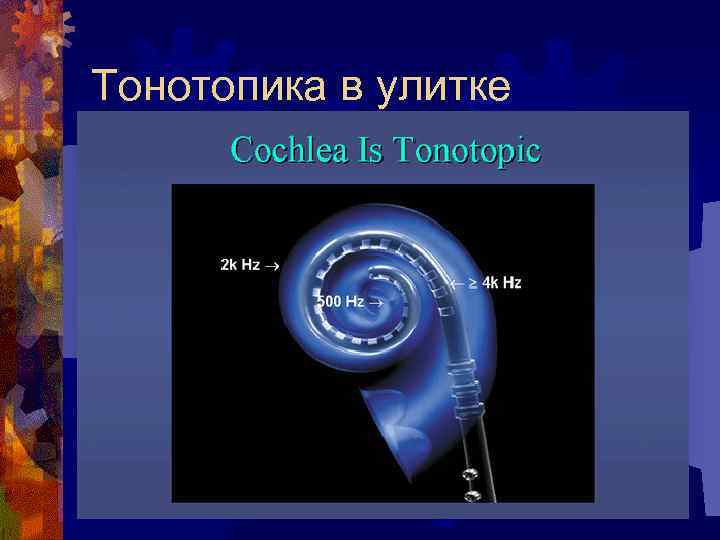

Тонотопика в улитке